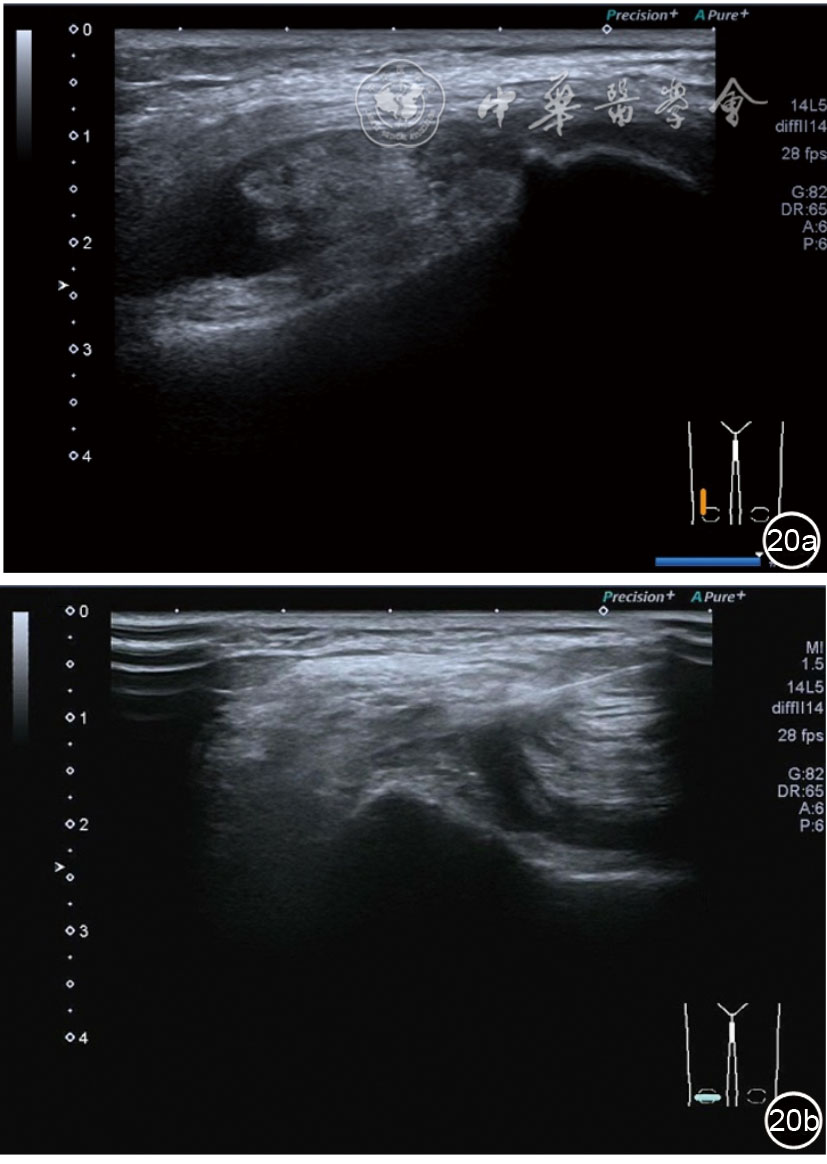

3.膝关节内局部治疗。随着病情发展,静态结构失衡,膝关节内部结构发生变化,会出现软骨损伤、脱落,关节间隙变窄,内外间隙不等,骨赘形成等。膝关节内局部治疗包括关节内症状性骨赘剥离、玻璃酸钠及PRP注射等。(1)膝关节内症状性骨赘针刀剥离松解治疗。由于软骨缺损或者力平衡失调,在关节内脱落软骨区会出现骨赘。部分骨赘引起疼痛,或者与髌骨撞击出现临床症状需要治疗。针刀剥离目的不是去除骨赘,而是剥离松解,缓解或者消除疼痛。以股骨外髁骨赘为例。患者平卧位,膝关节屈曲100°~120°。一般选用10 MHz超声探头,穿刺区域常规消毒,探头涂抹耦合剂后套入无菌手套碘伏消毒或使用无菌耦合剂。将探头置于患者皮肤表面,短轴扫查,显示关节面与骨赘,选用25G注射针,抽吸1%利多卡因3 ml于骨赘周围进行分层麻醉。选用直径1 mm的Ⅰ型2号针刀,在超声引导下从外侧向内侧到达骨赘,反复剥离,一般5~8刀后拔出针刀结束治疗(图18),局部压迫5分钟,无菌敷料覆盖。(2)膝关节髌上囊积液治疗。髌上囊积液在膝关节骨关节炎比较常见,尽管积液量可能很大,但通过软组织松解治疗后,大部分患者积液会减少或者消失。所以积液的治疗可以放在后面处理。超声引导下抽出积液,药物注射是常用的治疗方法。膝关节炎积液的治疗通常包括关节内皮质类固醇激素或者臭氧注射。如果慢性以滑膜丛型增生为主,针刀有限切割增生滑膜加药物注射可提高疗效。①髌上囊积液抽吸加臭氧注射治疗。患者平卧位,膝关节屈曲30°~60°,膝下垫一软枕。选用10 MHz超声探头,治疗前消毒准备同骨赘针刀剥离松解治疗。将探头置于患者皮肤表面,短轴扫查,找到积液最多处,应用22G针头,直接穿刺进入髌上囊抽出液体,然后根据髌上囊大小制备35 μg/L的15~20 ml臭氧注入髌上囊内拔出针头(图19),局部压迫2分钟,无菌敷料覆盖。②髌上囊慢性滑膜炎针刀切割松解治疗。患者平卧位,膝关节屈曲30°~60°,膝下垫一软枕。选用10 MHz超声探头,治疗前消毒准备同骨赘针刀剥离松解治疗。将探头置于患者皮肤表面,长轴或短轴扫查,找到积液最多处,用一次性5 ml注射器抽吸1%利多卡因3 ml于髌上囊进行分层注射麻醉,囊内也要注射适量麻药,尽量抽出积液。选用直径1 mm的Ⅰ型2号针刀,长轴扫查从近端向远端,短轴扫查从外侧向内侧,在超声引导下进入囊肿内对内壁及增生滑膜的不同方向、角度进行反复切割(图20),一般2~3分钟拔出针刀,然后囊内注射1%利多卡因3 ml+曲安奈德15 mg,结束治疗,局部压迫5分钟,无菌敷料覆盖。(3)膝关节腔PRP注射治疗。关节腔注射主要是为了修复软骨,如果不是为了治疗积液,不主张应用激素类药物。目前主要的注射药物为玻璃酸钠、PRP。按照传统的注射部位,多为髌上内、外或者髌下内、外注射点,但是超声不能观察到注射针的位置,药物也不能很好到达软骨损伤的部位,效果受到影响(图21)。膝关节软骨损伤的主要部位在髌股关节的股骨髁,超声可以很好地显示这一部位,并能显示软骨变薄。因此,由这个路径平面内进针注射,可以很好显示穿刺针的路径与位置。以注射PRP为例。患者平卧位,膝关节屈曲100°~120°,选用10 MHz超声探头,治疗前消毒准备同骨赘针刀剥离松解治疗。将探头置于患者皮肤表面,短轴扫查显示关节面,应用25G注射针头,抽吸1%利多卡因2 ml由内侧进针进行分层麻醉直达关节软骨面。制备4.5 ml PRP,直接注射到关节面,液体顺关节面分布,注射完毕拔出针头(图22)。局部压迫2分钟,无菌敷料覆盖。(4)髌骨软化超声影像融合技术下PRP注射治疗。髌骨软化是指髌骨关节面的软骨损伤,软骨下骨囊变,MRI能够明确诊断,但是超声不能显示。应用超声与MRI的影像融合技术,依据MRI明确注射部位,在超声引导下可将药物精准注射到软骨损伤的部位。患者平卧位,膝关节屈曲30°,下面垫一软枕。一般选用10 MHz超声探头,治疗前消毒准备同骨赘针刀剥离松解治疗。将MRI的原始图像数据导入超声设备中,进行手动影像融合,完全融合后,确定穿刺靶点,以MRI图像为目标,以超声图像为实时引导进行穿刺,到达目标后,注射提前制取的PRP 3 ml(图23),注射完毕拔出针头,局部压迫3分钟,创可贴覆盖。

图20 超声引导下髌上囊慢性滑膜炎针刀切割松解治疗

图21 传统膝关节注射方法超声图像